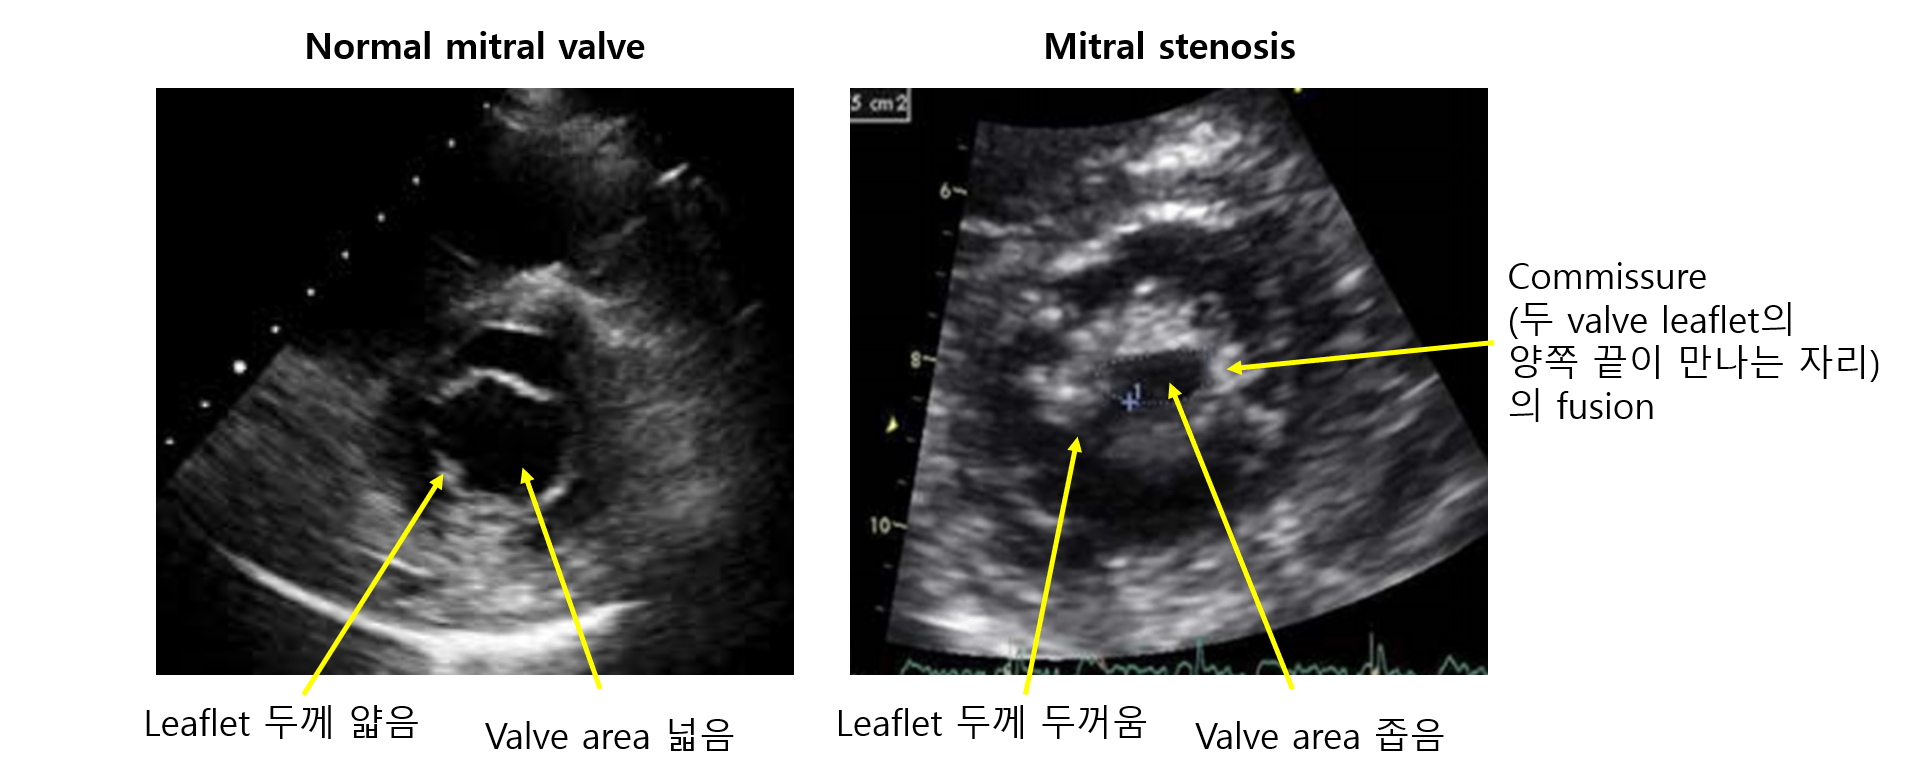

1) 경흉부심초음파(transthoracic echocardiography, TTE): 1st line

(1) MV area 감소: 협착으로 valve orifice가 좁아짐

(2) MV 형태: MV doming(hockey-stick appearance)

① 정상 MV: Diastole 때 MV가 곧게 뻗어 있거나, 휘어있어도 LA 쪽으로 휘어있음

② MV doming: Diastole 때 LA→LV 혈류의 강해진 힘에 의해 MV가 LV 쪽으로 밀려나 휘어버림

(3) LA enlargement, LA-LV 압력 차이 등

B | Progressive MS | Commissural fusion MVA > 1.5cm2 |